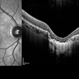

- hereditary retinal degeneration, hereditary retinal dystrophy, rod cone dystrophy

- Fundus autofluorescence of the left eye in a 58 yo male with rod cone dystrophy. He presented with night blindness and peripheral vision loss since youth and recent decrease in central vision for the past 10 years. Notice multiple coin shaped hypoautofluorescent pacthes within central 20 degrees which are coalescing centrally. (fundus photo uploaded separately) He has one pathogenic variants of both CEP290 and PRPH2 genes.